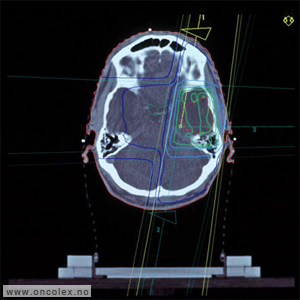

Eksempel på stråleplan

Strålefelt og isodosekurver ved stråleplanlegging av en hjernesvulst av type gliom i venstre tinninglapp.

Ut fra CT og MR defineres svulstområdet som skal strålebehandles, og i tillegg vil normalvevsstrukturer som er spesielt følsomme for stråling inntegnes. Disse strukturene kaller man risikoorganer og de innbefatter blant annet øyne, indre øre, synsnerver, synsnervekrysningen, hjernestamme og hukommelsessenteret. Disse viktige områdene og strukturene ønsker man å beskytte mot stråledose så godt det lar seg gjøre. Ved planlegging av strålebehandlingen vil stråleterapeuter, fysikere og leger samarbeide om å lage en best mulig plan for hver enkelt pasient. Målet er å gi tilstrekkelig stråledose mot svulsten, uten at man tar for stor risiko for stråleskade på risikoorganer og friskt hjernevev. Internasjonalt er det laget strenge dosekrav mot risikoorganer der man ønsker å redusere risikoen for senvirkninger, dette gjennomgås ved planlegging av hver enkelt plan.For å sikre best mulig kontroll over svulsten må man av og til akseptere noe økt risiko for senvirkninger. Om dette er aktuelt skal det diskuteres med hver enkelt pasient.